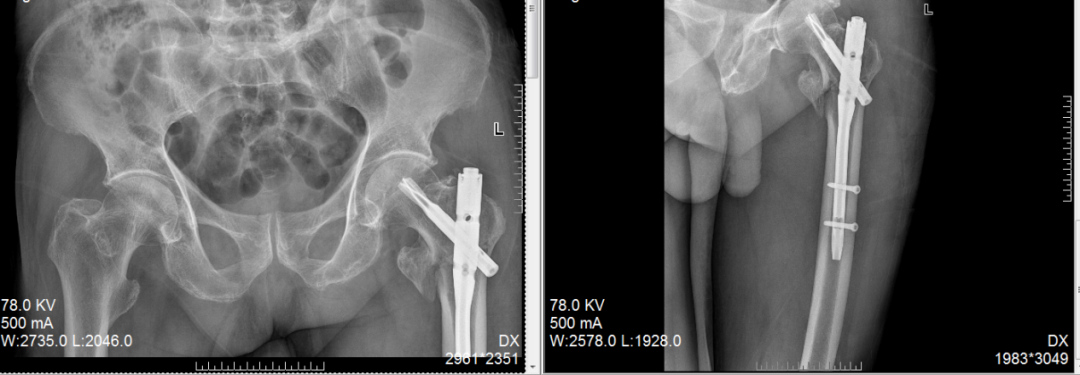

大腿多段骨折,一个小口完成修复

一位53女士大腿多处骨折,甚至影响到膝盖。我们仅在膝盖上方开一个约4厘米的小口,放入一根髓内钉将骨折处全部连接固定。这样既保护了腿部血流和肌肉,也为后期膝盖活动打下了好基础。